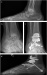

Die chirurgische Therapie der symptomatischen Sprunggelenksarthrose, vor allem bei jungen Patienten mit posttraumatischen Deformitäten, stellt eine große Herausforderung an den Fußchirurgen dar. Die Frage, ob und in welchen Fällen der Endoprothese oder der Arthrodese der Vorzug zu geben ist, bleibt nach wie vor unbeantwortet und die aktuelle Literatur trägt wenig zu ihrer Klärung bei. Nach den enttäuschenden Ergebnissen der ersten Generation von Sprunggelenksprothesen lassen nun die guten mittelfristigen Resultate der zweiten Generation aufhorchen. Nichtsdestoweniger steht der endgültige Nachweis ihrer Effektivität noch aus und es sind Langzeitstudien erforderlich, in denen die funktionellen Ergebnisse nach Endoprothesenimplantation denen nach Arthrodese gegenübergestellt werden müssen, um den Stellenwert der Sprunggelenksendoprothetik letztlich festzulegen.